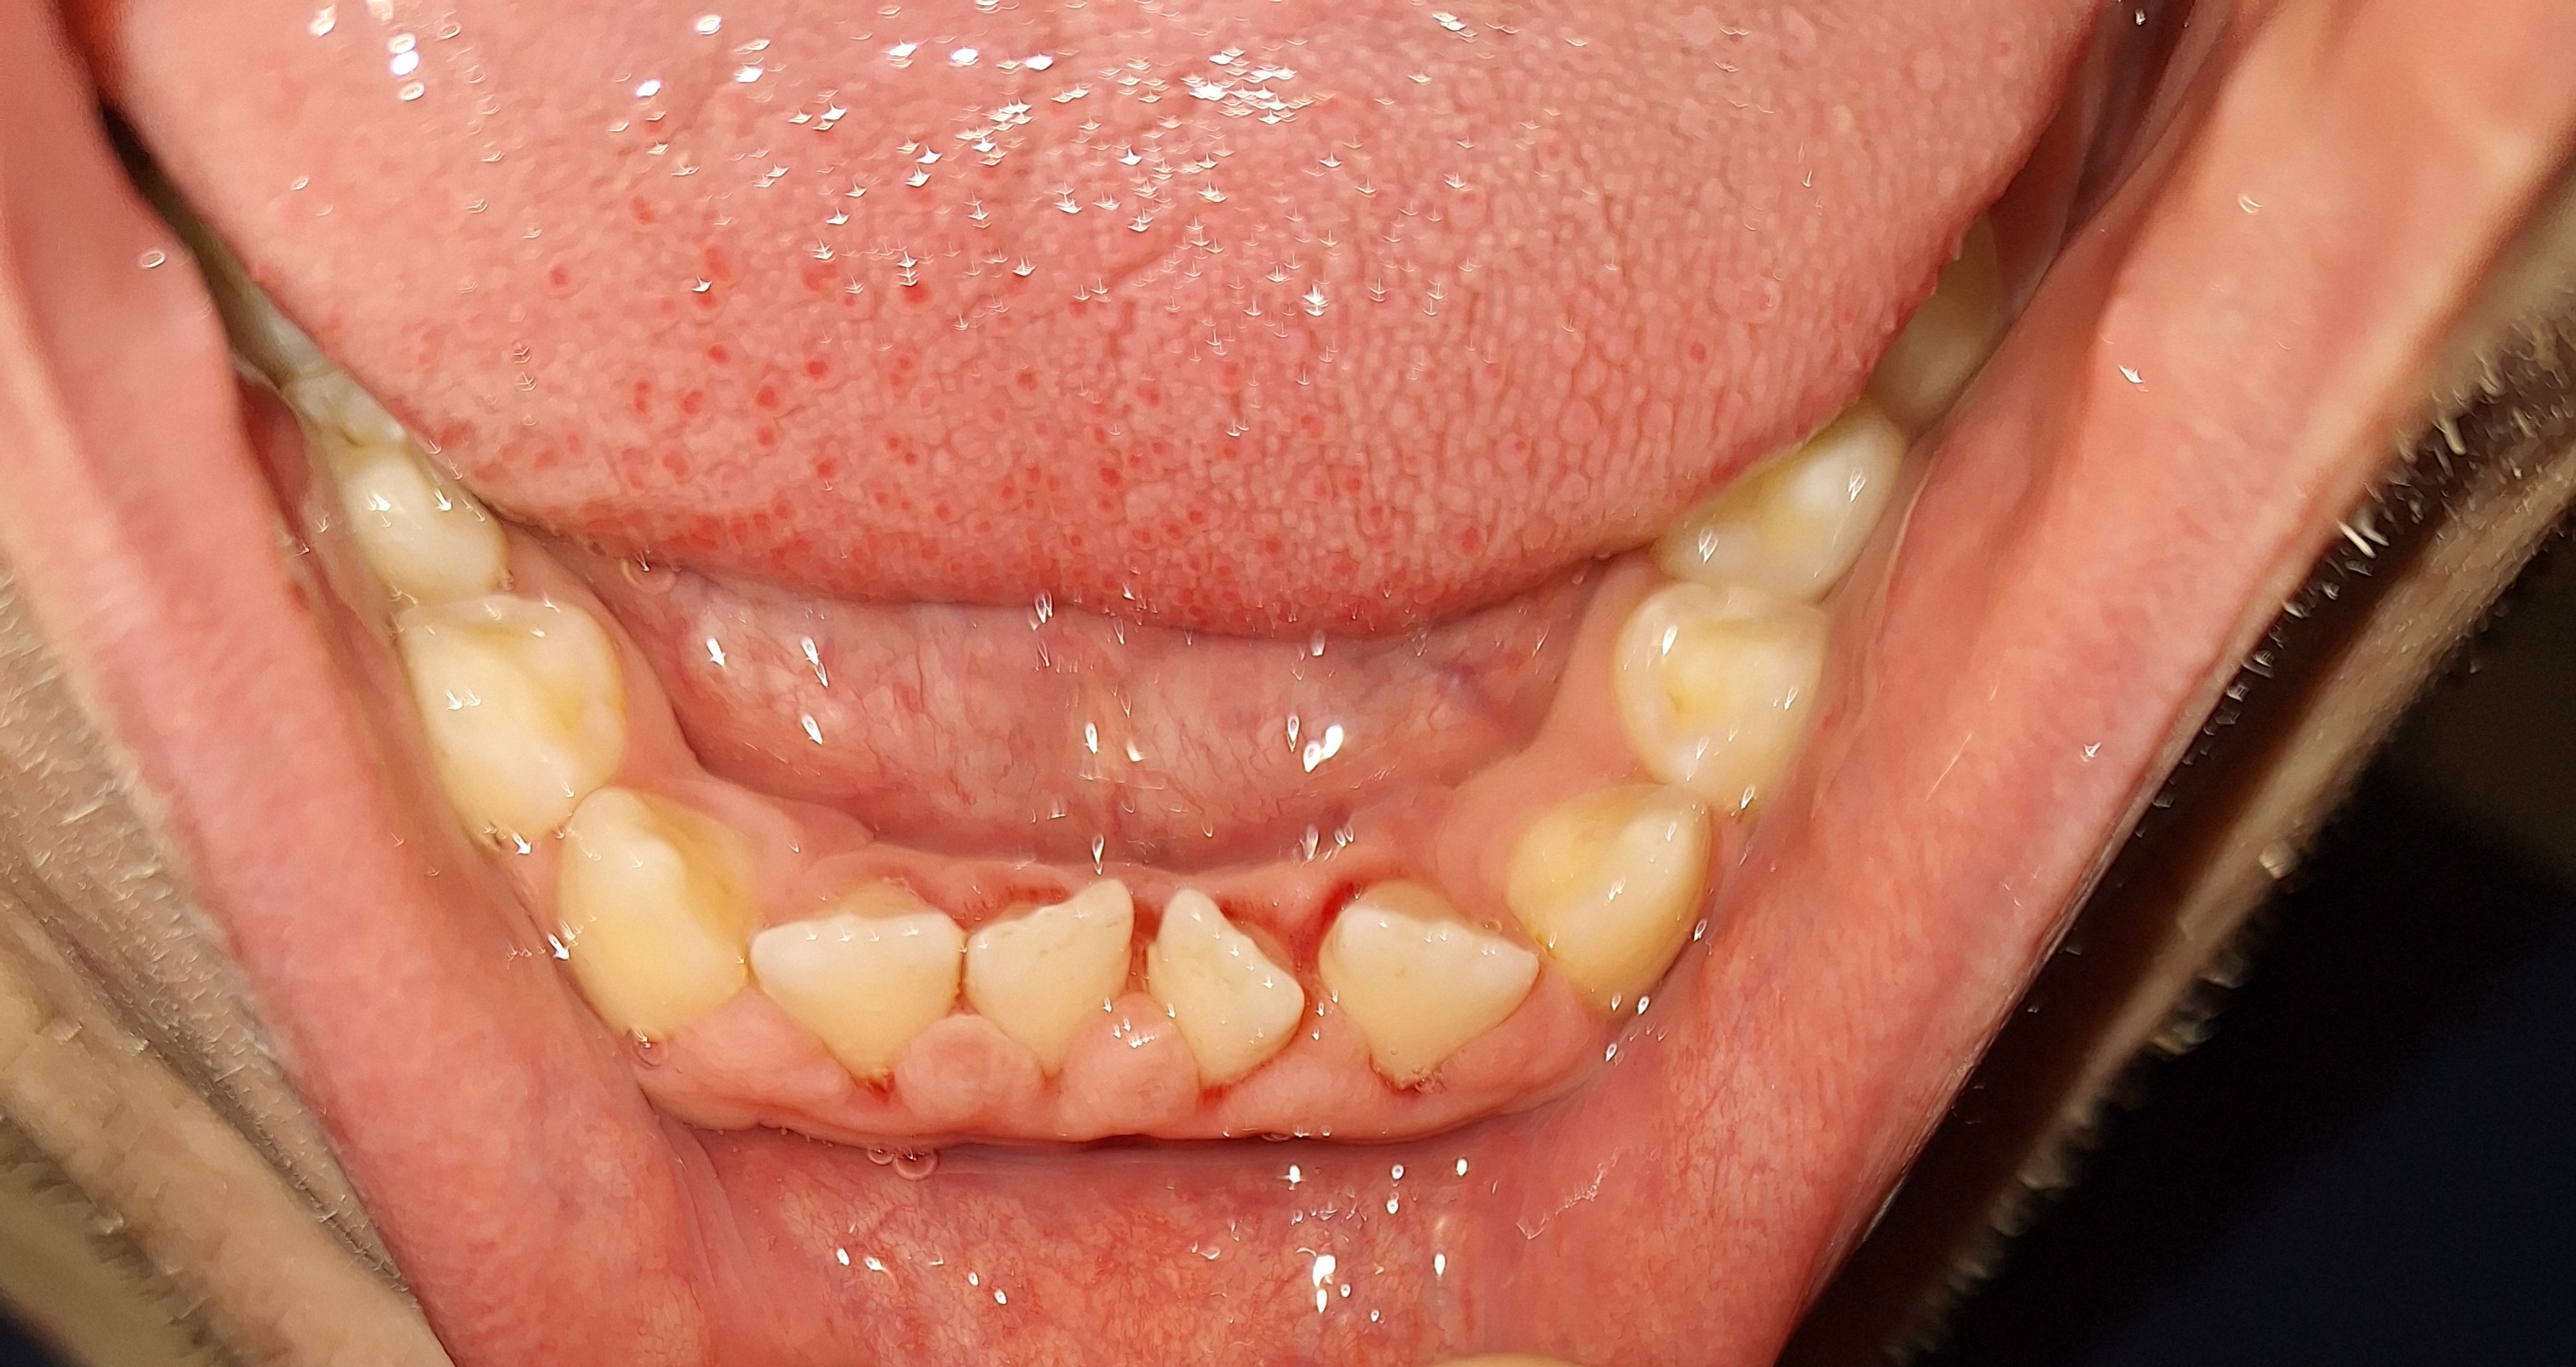

Сап медач.

Опустились дёсны в нескольких местах, обнажились шейки зубов. Чувствительные, болят от прикосновений, могут реагировать на холодное, горячее, сладкое.

Ситуация как примерно на пик2.

Предлагали два варианта:

1) Пластика десны, когда кусок кожи с нёба отрезают и пришивают к десне, чтобы закрыть оголившийся участок

2) Простое заделывание чувствительных мест пломбой/аналогом пломбы без пластики дёсен.

В первом случае меня беспокоит, что будет, если на оголившемся участке зуба есть кариес (сейчас из-за общей более тёмной природной пигментации шеек зубов + налёта не понятно), и я зашью этот кариес под кожу? Кариес будет прогрессировать под десной?

А во втором случае, дохтур сказал, что к заделанным пломбой шейкам зубов десна уже назад не прирастёт, даже если пересадить, то есть пластика дёсен будет невозможна.

ЧТО ДЕЛАТЬ, КАК ЛУЧШЕ ПОСТУПИТЬ?